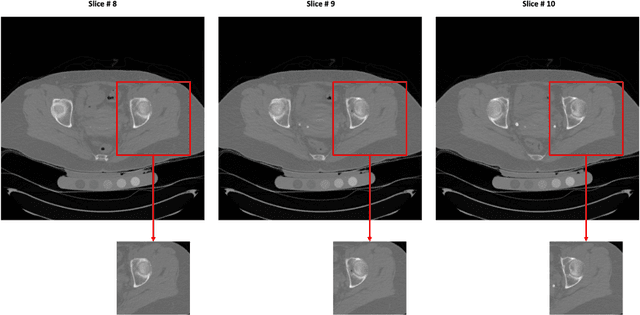

Abstract:Purpose: Proximal femur image analyses based on quantitative computed tomography (QCT) provide a method to quantify the bone density and evaluate osteoporosis and risk of fracture. We aim to develop a deep-learning-based method for automatic proximal femur segmentation. Methods and Materials: We developed a 3D image segmentation method based on V-Net, an end-to-end fully convolutional neural network (CNN), to extract the proximal femur QCT images automatically. The proposed V-net methodology adopts a compound loss function, which includes a Dice loss and a L2 regularizer. We performed experiments to evaluate the effectiveness of the proposed segmentation method. In the experiments, a QCT dataset which included 397 QCT subjects was used. For the QCT image of each subject, the ground truth for the proximal femur was delineated by a well-trained scientist. During the experiments for the entire cohort then for male and female subjects separately, 90% of the subjects were used in 10-fold cross-validation for training and internal validation, and to select the optimal parameters of the proposed models; the rest of the subjects were used to evaluate the performance of models. Results: Visual comparison demonstrated high agreement between the model prediction and ground truth contours of the proximal femur portion of the QCT images. In the entire cohort, the proposed model achieved a Dice score of 0.9815, a sensitivity of 0.9852 and a specificity of 0.9992. In addition, an R2 score of 0.9956 (p<0.001) was obtained when comparing the volumes measured by our model prediction with the ground truth. Conclusion: This method shows a great promise for clinical application to QCT and QCT-based finite element analysis of the proximal femur for evaluating osteoporosis and hip fracture risk.